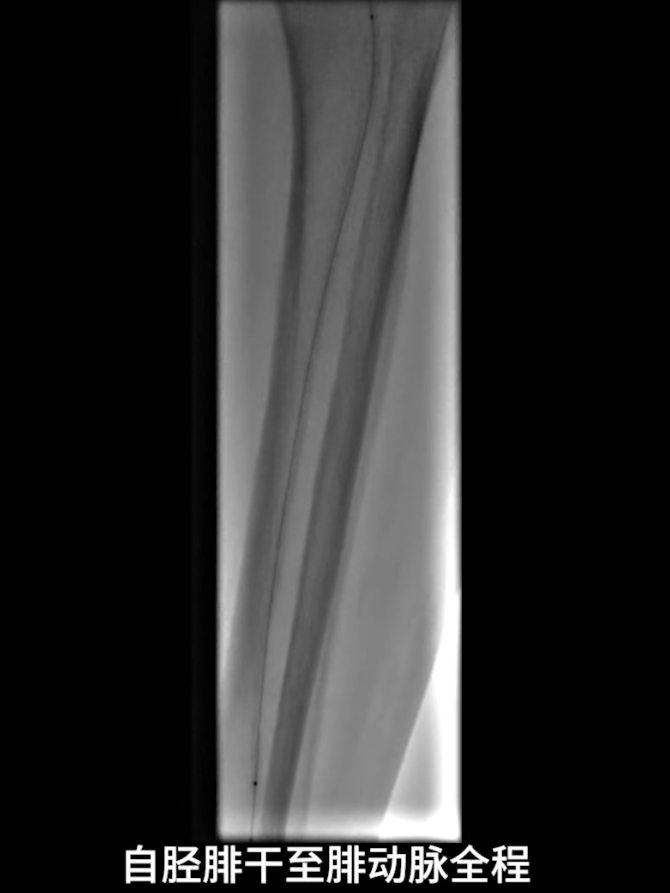

左侧股浅动脉中上段明确长段狭窄并闭塞,病变长度约15cm,股浅动脉远段至腘动脉管腔通畅。

膝下动脉三支主干均闭塞,胫后动脉远端经侧支循环显影;腓动脉远端为“休眠血管”,通过与胫后动脉的交通支实现逆向显影。